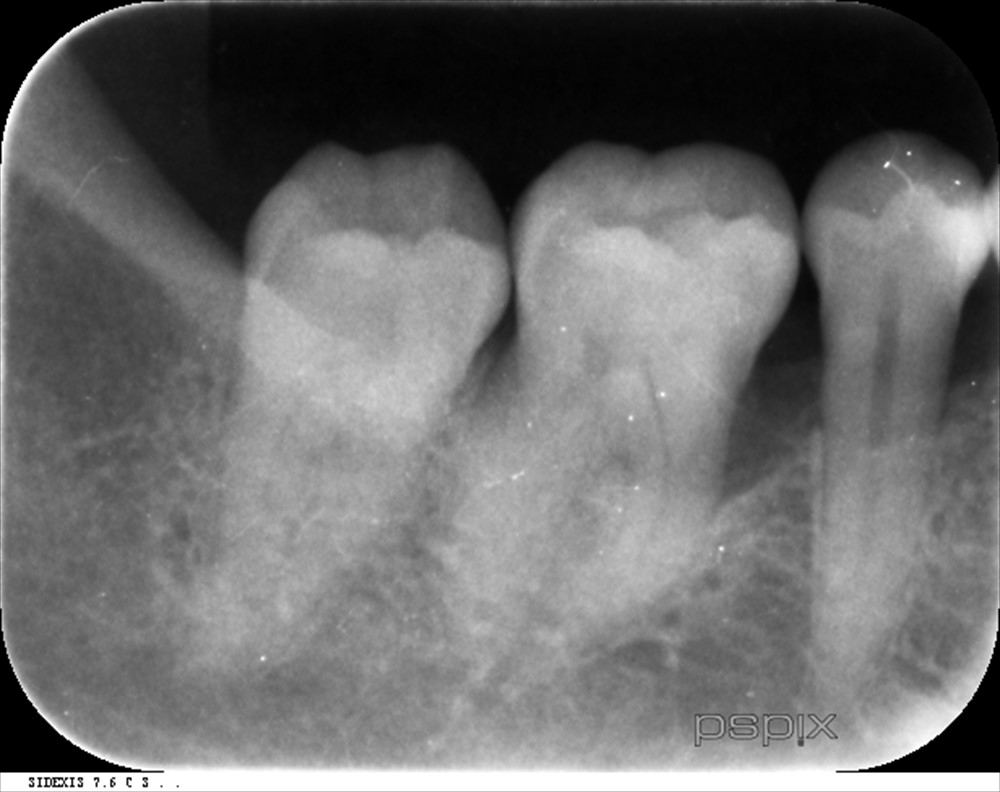

術後6ヶ月レントゲン↓

術前↓

再生が認められます。

ポケットも3~4mmで落ち着き出血もありません。